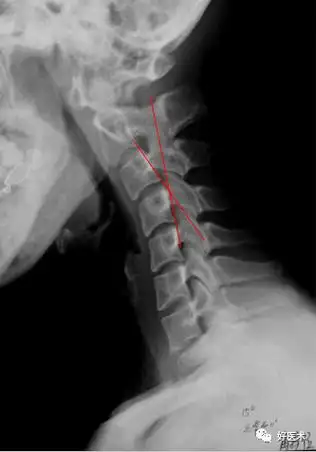

颈椎病解剖,经典影像改变,看这一篇就够了!